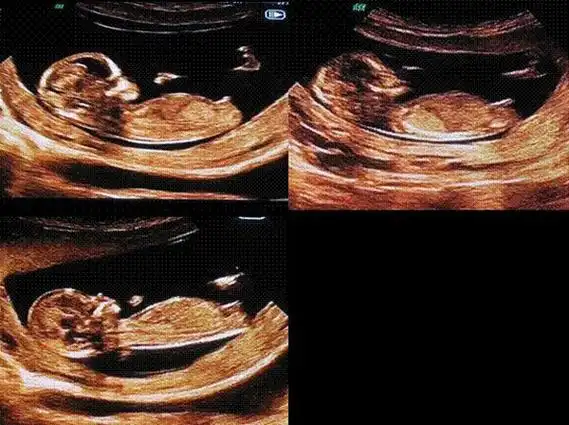

怀孕12周男女区别图怀男孩女孩nt单子揭秘2